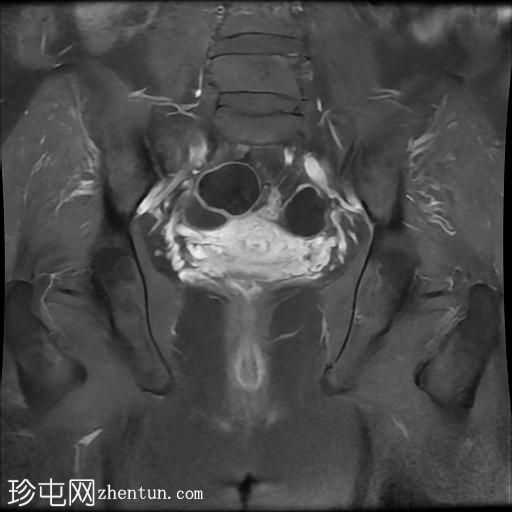

冠状位

T1加权像

右侧输卵管呈管状囊性扩张,直径达30 mm,提示输卵管积水,呈均匀液体信号,无实性成分。

左侧输卵管亦有轻度扩张,直径26 mm,符合输卵管积水表现。

右侧卵巢可见一单纯性卵巢囊肿,大小约35 x 40 mm,呈正常液体等效信号。

宫内节育器位置正常。

MRI 检查结果显示双侧输卵管积水和右侧卵巢单纯性囊肿。总体而言,所有附件和盆腔检查结果均显示良性 MRI 特征(O-RADS 2 类),无恶性肿瘤迹象。